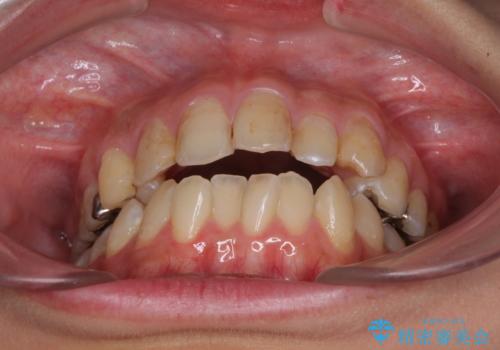

後戻りを治したい 骨格的なズレの大きい方のインビザライン矯正

- 中学生の時に矯正治療をしたものの、後戻りを気にして来院された患者様です。

骨格的に下顎が右側に変位しているため、左右の咬み合わせを理想的なものに改善することはできませんが、インビザラインにて歯列を整えることとしました。

骨格的なズレによる左右差は改善できませんでしたが、上下の正中を極力合わせるようにすることができました。